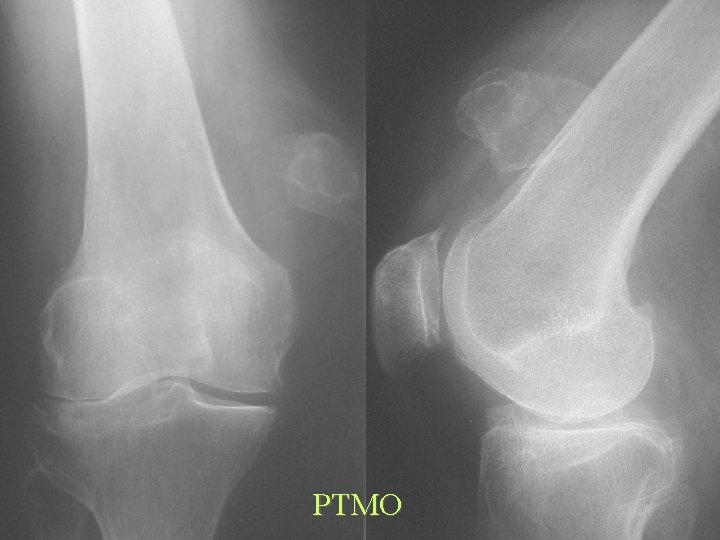

PTMO

Post Traumatic Myositis Ossificans Centrifugal Ossification Neoplastic Soft Tissue Ossification Centripetal Ossification

Ossification Traumatic Tendons and Ligaments • Calcification common, Ossification rare • • • MCL knee - Pellegrini-Stieda Coracoclavicular Achilles tendon Supraspinatus Stylohyoid ligament XS - Eagle syn.